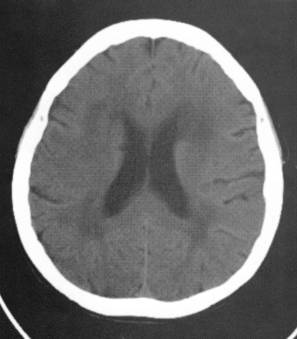

【病例讨论】ct表现为稍高密度的脑白质病变,性质? [病例帖]

3种常见脑白质病ct表现

脑白质疏松症的诊断和鉴别诊断